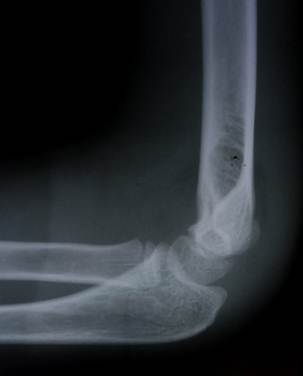

Снимок локтевого сустава ребенка в возрасте 1 года. Заметно ядро

окостенения головчатого возвышения и латерального вала блока плечевой кости.

Ребенок в возрасте 2 лет. Ядро окостенения головчатого возвышения

увеличилось и стало шире. На метафизарной зоне можно увидеть небольшую плоскую

площадку – зону медиального надмыщелка.

Возраст 3 года. Появилось адро окостенения головки лучевой кости.

Площадка медиального надмыщелка отчетливо контурируется.

Возраст 6 лет. Появилось ядроокостенения медиального надмыщелка.

Хорошо прослеживаются основания венечного и локтевого отростков. На прямом

снимке тень локтевой кости находится

выше уровня суставной щели.